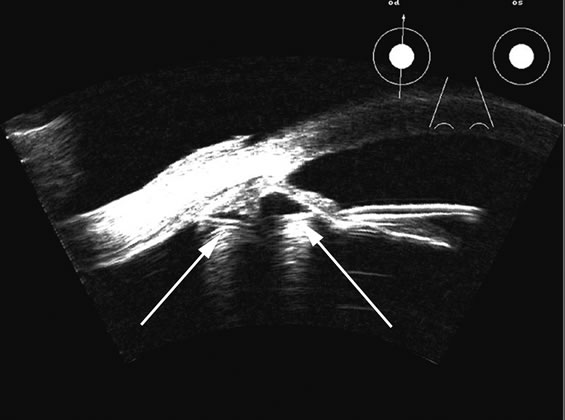

Fig. 4. A clinically well-placed posterior chamber intraocular lens nevertheless had patient complaints of photophobia and irritation due to a folded haptic (arrow).

Fig. 5. An anterior chamber intraocular lens has had the support haptics dislocate posterior to the iris plane and can be seen as typical foreign body echogenic reflections (arrows).